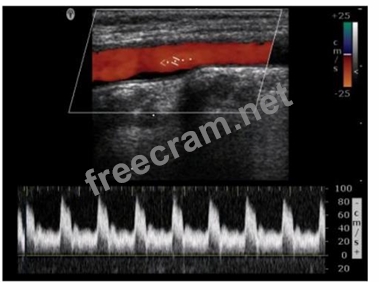

Which adjustment would reduce the noise in the Doppler waveform in this image?

Question 14: Which adjustment would reduce the noise in the Doppler wavef...